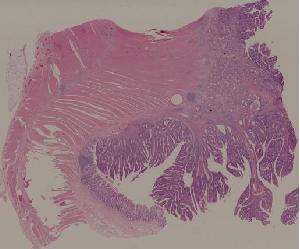

29. Adenocarcinoma of the colon